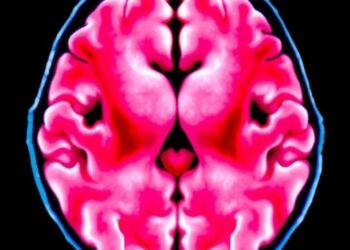

Brain Metastases in Metastatic Breast Cancer

In a groundbreaking analysis of real-world data from the United States, researchers have illuminated the complex landscape of brain metastases ...